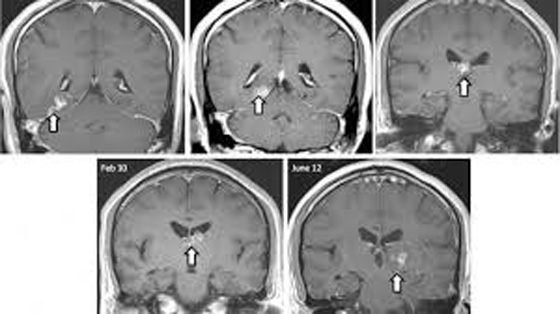

استخرج أطباء بريطانيون دودة من دماغ رجل بريطاني، طولها سنتيمتر واحد، بعدما ذهب لاستشارة طبيب ومعاينته نتيجة صداع حاد كان يعاني منه. وكانت هذه الدودة تنتقل من مكان إلى آخر في دماغ الرجل الخمسيني منذ نحو السنة، وفق ما أكّده باحثون في 21 من هذا الشهر، وتعرف هذه الدودة باسم Spirometra erinaceieuropei.

هذه المرّة الأولى التي يتمّ من خلالها اكتشاف هذا النوع من الطفيليات في بريطانيا. فمنذ العام 1953 تمّ تسجيل 300 حالة فقط في جميع أنحاء العالم. تسببّ هذه الدودة التهاباً في الخلايا، وإن وصلت إلى الدماغ، يصبح هناك فقدان للذاكرة وآلام في الرأس. إنّ هذا النوع النادر يبقى غامضاً في نظر الباحثين الذين يجهلون دورة حياته. يلتقط الإنسان هذا النوع من خلال تناوله لحيوانات مائية. وقد أعطيت لاختصاصيين من الـ Wellcome Trust Sanger Institute في كامبريدج الذين تمكنوا من استخلاص جينومه للمرّة الأولى، ممّا يسمح لهم باكتشاف علاج له.